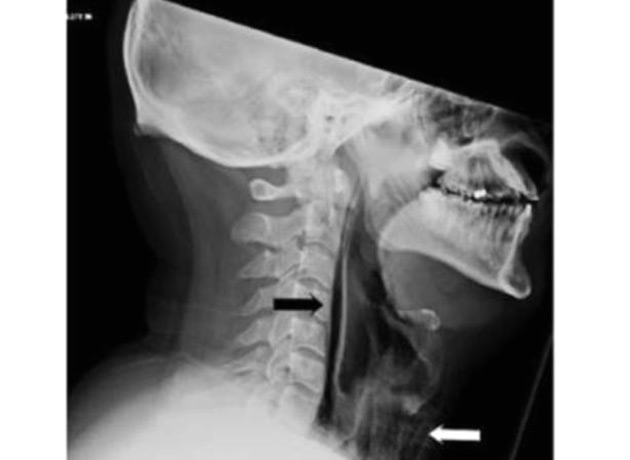

Los escaneos confirmaron el problema. Las pruebas mostraron vetas de aire reales en la región retrofaríngea y enfisema quirúrgico extenso en el cuello anterior a la tráquea. En otras palabras, al tratar de retener su estornudo, en realidad se hizo un pequeño agujero en la garganta.